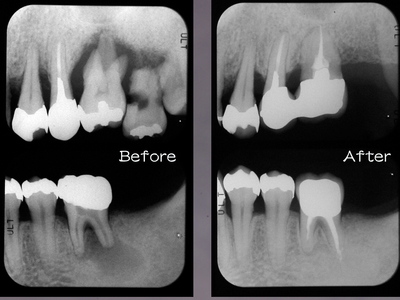

メンテナンスに移行

急発〜挺出〜咬合性外傷 で上顎前歯は抜けそうでしたが、なんとか助かりました。右上1右下2近心のX-P像に注目ください。動的治療期間2年弱ですからまあまあでしょう。

今回の連載には間に合わなかったため治療経過詳細はいずれ別の機会に。